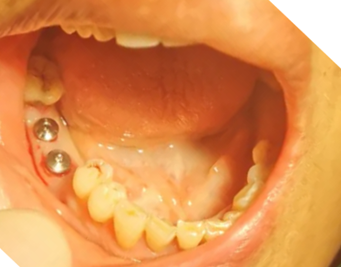

張教授采用美國目前流行的微創(chuàng)種植手術(shù),在短短的10來分鐘內(nèi),完成2顆JTK金泰克種植牙的植入手術(shù),贏得了醫(yī)護人員及患者的當眾稱贊!患者當場表示驚訝,并要求醫(yī)生再撥掉另外兩顆已經(jīng)搖動的恒牙,下期再種!

金泰克種植體的微創(chuàng)手術(shù),不僅能極大縮短手術(shù)時間,減少病人的痛苦和手術(shù)感染的風(fēng)險,也減少牙醫(yī)在手術(shù)臺上的體力耗損,而且微小的創(chuàng)口也讓無痛植牙技術(shù)成為現(xiàn)實,病人手術(shù)體驗極佳。